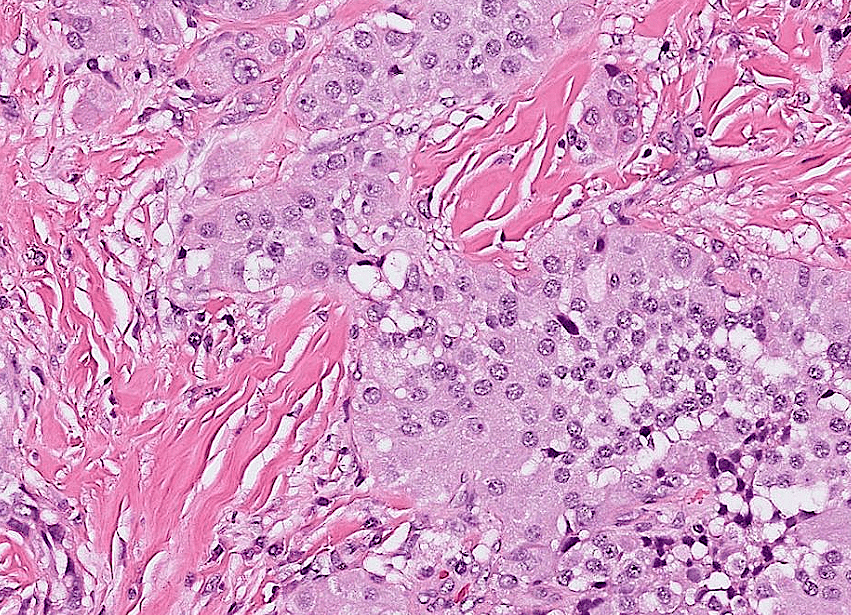

hepatocellular carcinoma